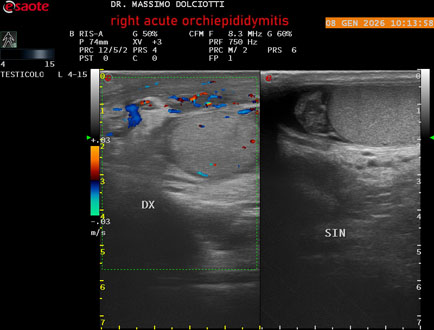

Data inserimento: 08/01/2026

Ecografia del: 08/01/2026

Strumento: Esaote MyLab Eight

Sonda: Lineare Multifrequenza 4-15 MHz

Età Paziente: M 74 anni

Motivazione dell'esame: da 3 giorni dolore e tumefazione al testicolo destro.

Commento all'esame: le immagini ed il video documentano il didimo destro, aumentato di volume, con incremento della vascolarizzazione; aumentato di volume e di vascolarizzazione anche l'epididimo destro, Normale il didimo sin e l'epididimo sinistro, Gli elementi ecografici segnalati orientano per orchiepididimite destra acuta.

Conclusioni: orchiepididimite destra acuta (right acute orchiepididymitis).

Presentazione: Dr. Massimo Dolciotti - Ancona